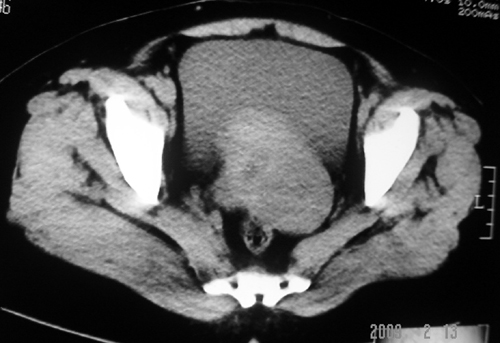

以下是引用余辉在2009-2-14 8:37:00的发言:[br]宫颈左后壁见较大低密度肿物影且向左后上方突出,宫腔内见大片状低密度区,考虑宫颈肿瘤,宫颈癌可能性大,伴宫腔积液或转移